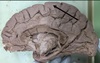

Not at all

1. Identify 2 2. Identify 3 3. Identify 4 4. Identify 5 5. Identify 6

1. Falx Cerebri 2. Corpus callosum 3. Midbrain 4. cerebellum, grey matter 5. basilar artery